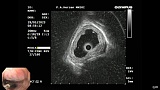

Иллюстрация №3: Эндофото. Сидероз нижней трети пищевода, эндоскопическая ультрасонография

Согласно полученным данным - в среднегрудном и нижнегрудном отделах пищевода определялась проксимальная граница плоских неправильной формы поверхностных рубцов суммарной протяженностью до 8,0 см. На этом фоне в зонах поверхностных рубцов по задней полуокружности визуализировались участки гиперпигментации в темный цвет (Рис. 1). При исследовании в режиме Dual Focus было отмечено наличие мелких (до 0,001 см) черно-коричневых включений, расположенных субэпителиально - в строме слизистой оболочки, сливания их в единый конгломерат не определялось (Рис. 2). При эндосонографии с применением минидатчика с частотой сканирования 20МГц выявлено, что все слои стенки четко дифференцируются, не утолщены, в слизистой оболочки визуализированы мелких гиперэхогенные включения с эхотенями (Рис. 3).

В пищеводе в шейном его отделе на уровне 16 см от резцов циркулярно визуализированы единичные синюшные флебоэктазии размерами до 0.5 см. Дистальнее пищевод визуально не изменен до уровня 28 см от резцов, где определяется проксимальная граница плоских неправильной формы поверхностных рубцов, распространяющихся до уровня 36 см от резцов. На этом фоне в зонах поверхностных рубцов по задней полуокружности визуализированы участки гиперпигментации в черно-коричнеый цвет. При осмотре в режиме Near Focus с увеличением - между зон пигментации определяются расширенные капилляры типа II по Inoue-классификации. При биопсии отмечена десквамация плоского эпителия, визуализированы мелкие черно-коричневые включения в строме слизистой оболочки, размеры их до 0,001 см, сливания их в единый конгломерат не отмечается. При эндосонографии с датчиком 20Мгц в исследуемой зоне в слизистой оболочке определяются гиперэхогенные включения, в то время как в подслизистом слое - зоны со сниженной эхогенностью. При биопсии отмечается уплотнение ткани, однако истинной фрагментации не определяется. Уровень Z-линии совпадает с уровнем анатомического кардиоэзофагеального перехода. Розетка кардии эластичная, смыкается не полностью, расположена на уровне пищеводного отверстия диафрагмы.